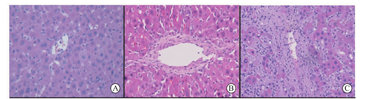

在三组受鼠死亡或者观察期结束后,受鼠的移植肝被立即取出并行HE染色。A组观察到门静脉周围出现胆管增生,有少量的淋巴细胞浸润,肝窦未见明显扩张。在中心静脉区未观察到内皮的增生,周围肝窦有淋巴细胞浸润。B组门静脉周围可以同样观察到胆管上皮的增生,淋巴细胞的浸润,肝窦稍有增宽,但没有明显的扩张。在中央静脉区可观察到内皮明显增厚,周围伴有淋巴细胞浸润,提示血管炎症反应。C组死亡受鼠肝脏组织中可以看到门静脉周围大量的淋巴细胞浸润,肝窦明显扩张,被浸润的淋巴细胞充填。正常的肝细胞排列形态被破坏。中心静脉附近同样可见大量淋巴细胞浸润。血管内皮明显增厚。上述组织学表现提示C组受鼠死于急性排斥反应(图3)。C组的Banff RAI评分明显高于A组和B组,C组为9.0±0.0 ,A组为5.0±1.1,B组为6.0±1.4(P<0.05),而B组和A组间Banff RAI评分的差异无统计学意义(表3)。

B1、C1组受鼠根据GW/RLW分组,组间GW/RLW差异亦具有显著统计学意义(P<0.01,表1)。移植肝脏在术后的第7天被取出,并行HE染色行组织学分析。两组均可以观察到肝窦扩张,肝窦内门静脉区有较多的淋巴细胞浸润,血管内皮也可见淋巴细胞浸润,提示移植排斥反应的发生,B1、C1组Banff RAI评分分别为8.5±0.5和7.5±0.8,组间差异未见统计学意义(P>0.05,表3,图4),可能是由于均处于急性排斥反应病理变化的早期。